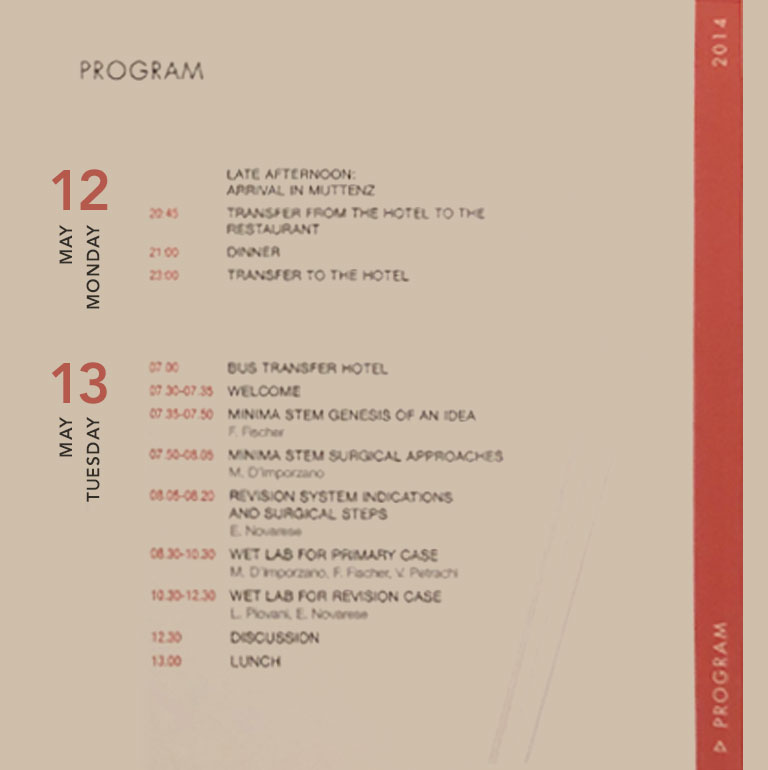

Lima Life Long Learning - Tutor

Lima Life Long Learning - TutorRevision System Indications

and Surgical Steps -

Lima Life Long Learning - Tutor

Lima Life Long Learning - TutorRevision System Indications

and Surgical Steps